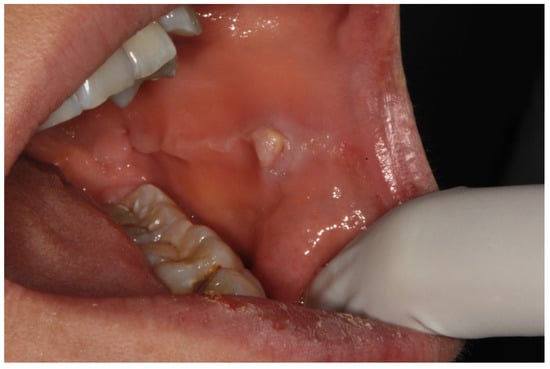

- According to the types and lesions pattern, oral mucosa pathologies are observed in different sites of oral cavity, both in single or multiple localizations and both symmetrically and non-symmetrically.